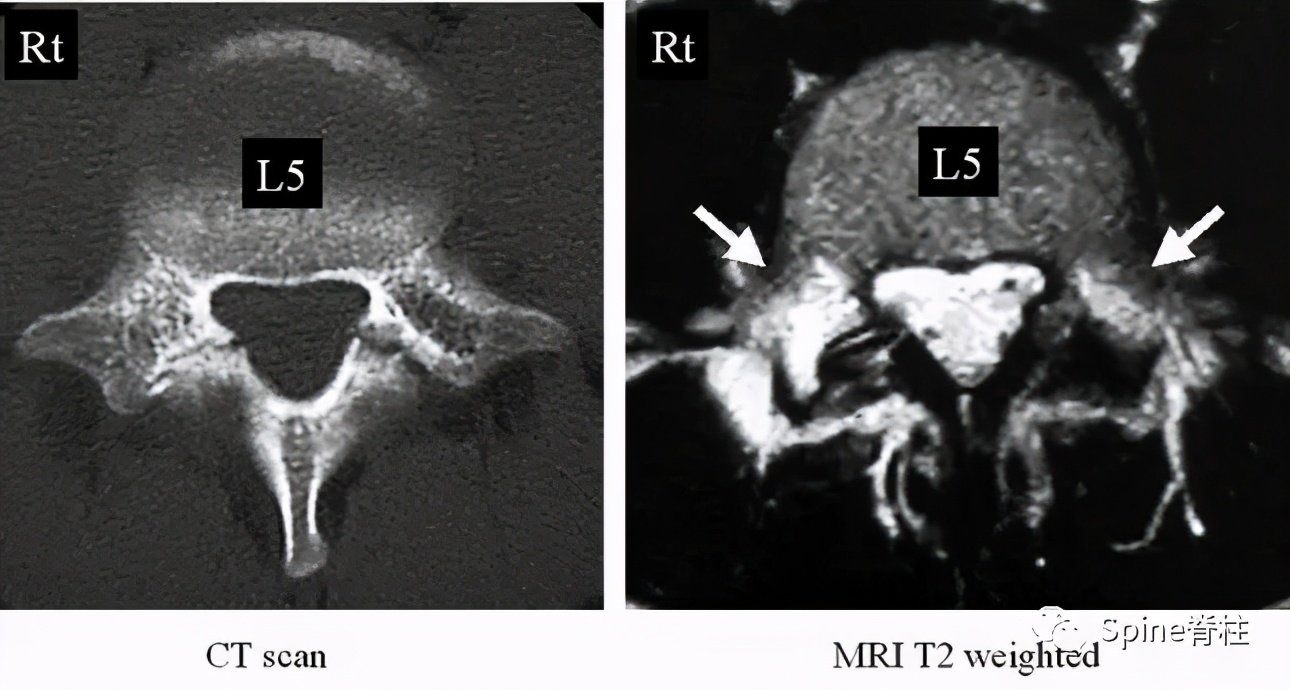

图:17岁男孩,因“腰痛伴右下肢放射痛6个月”就诊

MRI提示腰5-骶1椎间盘突出

青少年与成人LDH都可出现腰腿痛,但 青少年LDH症状通常较轻,神经功能损害(如感觉障碍、肌力下降等)较少见 ,而直腿抬高试验阳性率则可高达90%,而且常呈强阳性,多限于<30°范围。

与成人LDH相比, 青少年LDH患者出现腰椎畸形的比例较高,常见腰部僵硬、脊柱侧凸或旋转,常凸向患侧 ,这种畸形通常是由于疼痛而产生的代偿性脊柱侧凸。

对于以脊柱侧凸为首诊原因的青少年LDH,如果误诊误治会造成严重后果。 此外,腰椎关节突关节不对称的发生率也明显高于成人LDH。

青少年LDH通常仅累及1个节段,最常见于L4-5,少有伴随Modic改变。

青少年LDH以中央型多见,突出物较大,常包含部分骨性结构, 突出的髓核退变不明显,钙化、骨化少见。